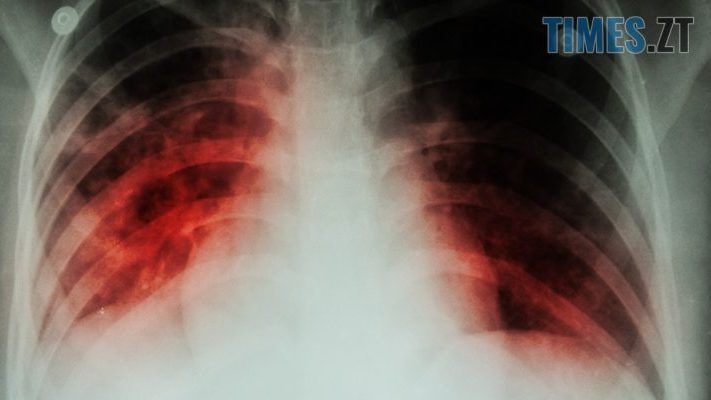

Лише за поточний 2019 рік в місті туберкульозом заразилися 82 людини, 8 з яких — діти. На обліку в Житомирі з цією страшною вірусною інфекцією офіційно перебуває 800 пацієнтів. З них 300 хворих мають активну форму туберкульозу, а близько 100 — мультирезистентну. За статистикою щороку на туберкульоз заражаються в середньому 120 житомирян.

В Україні та Житомирі зокрема, про епідемію туберкульозу не перестають говорити ще з 1995 року. Майже 25 років смертельно небезпечна хвороба підточує здоров’я житомирян. За кількістю випадків туберкульозу Україна посідає друге місце в Європі.